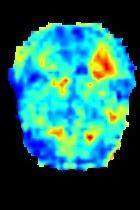

Current unsupervised anomaly localization approaches rely on generative models to learn the distribution of normal images, which is later used to identify potential anomalous regions derived from errors on the reconstructed images. However, a main limitation of nearly all prior literature is the need of employing anomalous images to set a class-specific threshold to locate the anomalies. This limits their usability in realistic scenarios, where only normal data is typically accessible. Despite this major drawback, only a handful of works have addressed this limitation, by integrating supervision on attention maps during training. In this work, we propose a novel formulation that does not require accessing images with abnormalities to define the threshold. Furthermore, and in contrast to very recent work, the proposed constraint is formulated in a more principled manner, leveraging well-known knowledge in constrained optimization. In particular, the equality constraint on the attention maps in prior work is replaced by an inequality constraint, which allows more flexibility. In addition, to address the limitations of penalty-based functions we employ an extension of the popular log-barrier methods to handle the constraint. Comprehensive experiments on the popular BRATS'19 dataset demonstrate that the proposed approach substantially outperforms relevant literature, establishing new state-of-the-art results for unsupervised lesion segmentation.